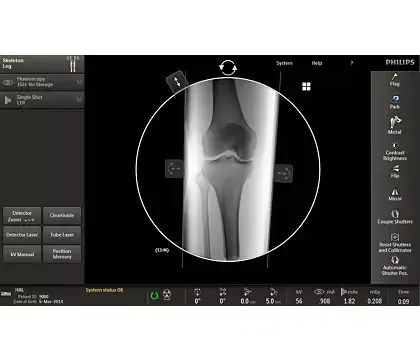

Клинические изображения

Philips Veradius Unity — улучшенное качество изображения и удобство работы в мобильной хирургии с новой плоскопанельной С-дугой.

Расширенный спектр применения Philips Veradius Unity возможен благодаря оптимальному размеру рабочего поля аппарата, компактности и легкости конструкции и увеличенной глубине С-Дуги до 73 см.

Philips Veradius Unity может полноценно работать как в отделениях ортопедии, электрофизиологии, онкологических отделениях при проведении биопсии, дренирования, нейролизиса, так и в отделениях, занимающихся диагностикой и лечением сосудистых заболеваний, включая кардиологические

Новый динамический плоский детектор 27×27 см позволяет получать изображение с гораздо более качественным изображением по сравнению с традиционными усилителями изображения.